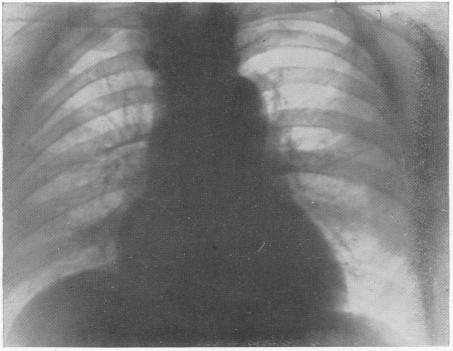

THE EFFECT OF OBSTRUCTED RESPIRATION ON HEART AND LUNGS: ITS CLINICAL IMPORTANCE IN RADIOGRAPHY.

Br Med J. 1929 Mar 9;1(3557):439-438.2. doi: 10.1136/bmj.1.3557.439.